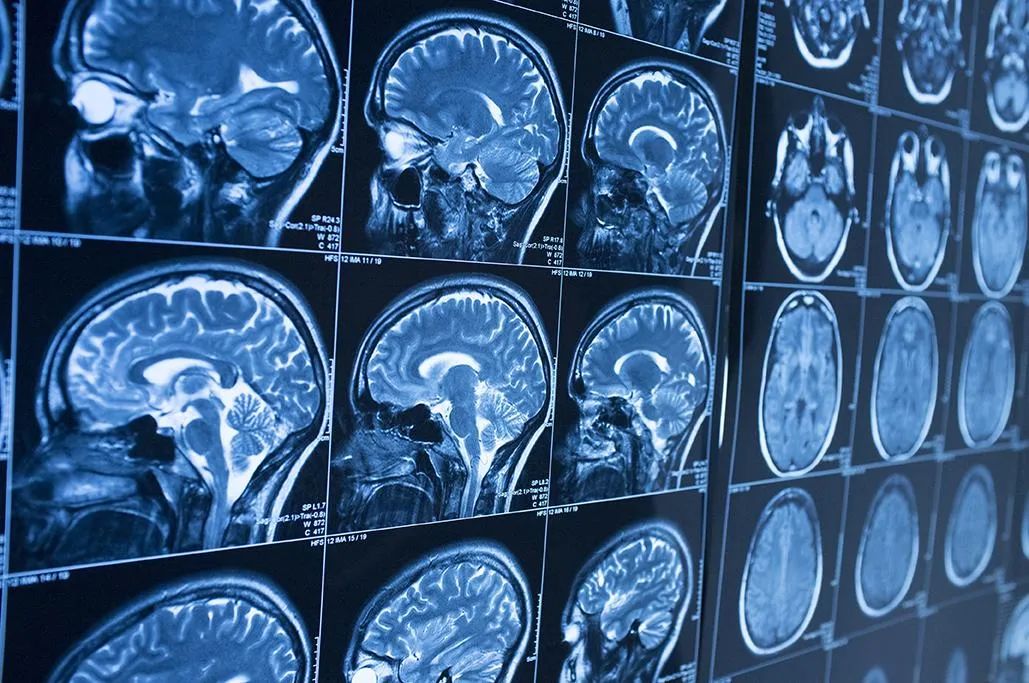

阿尔茨海默症目前是根据PET扫描或脑脊液分析的结果诊断的,但是与这两个金标准相比,血液检测的侵入性更小、成本更低,因此在诊断和管理阿尔茨海默症方面发挥重要作用。与此同时,生物标记物的发现和检测的进步使检测患者血液中与阿尔茨海默症相关的分析物成为可能,提高了诊断的可能性,从而可以在大规模、潜在无症状的人群中低成本和大规模地进行。